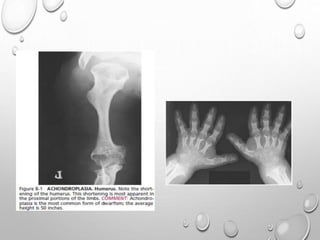

ACHONDROPLASIA

FAILURE OF NORMAL ENCHONDRAL CARTILAGE GROWTH AT

PHYSIS

PERIOSTEAL , MEMBRANOUS OSSIFICATION ARE NORMAL

• MOST COMMON TYPE OF DWARFISM

• AUTOSOMAL DOMINANT DISORDER AND THE MAJORITY OF

LIMBS

UL> LL

RHIZOMELIC TYPE

METAPHYSIS …..SPLAYING , CUPPING

GENU VERUM

TRIDENT HAND

TIBIA , ULNA ARE MORE SHORTENED THAN FIBULA , RADIUS

V SHAPED NOTCH IN GROWTH PLATE

SHORT , TUBULAR LONG BONES OF HAND AND FEET

FINGERS ARE OF SAME LENGTH